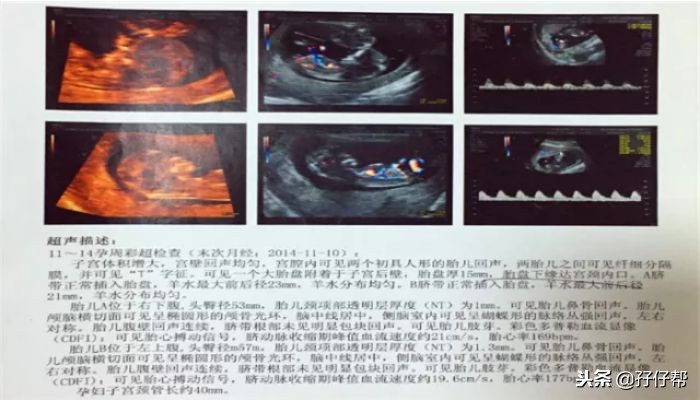

据之前了解的信息,单绒双羊可是TTTs的重灾区啊!我的NT报告单如下图(1)⏬⏬

下图(2)⏬⏬

NT 结果挺好的,只是有一个宝宝胎心偏快,177次/分。胎盘目前处于前置状态,两胎宝宝孕周相差两天。